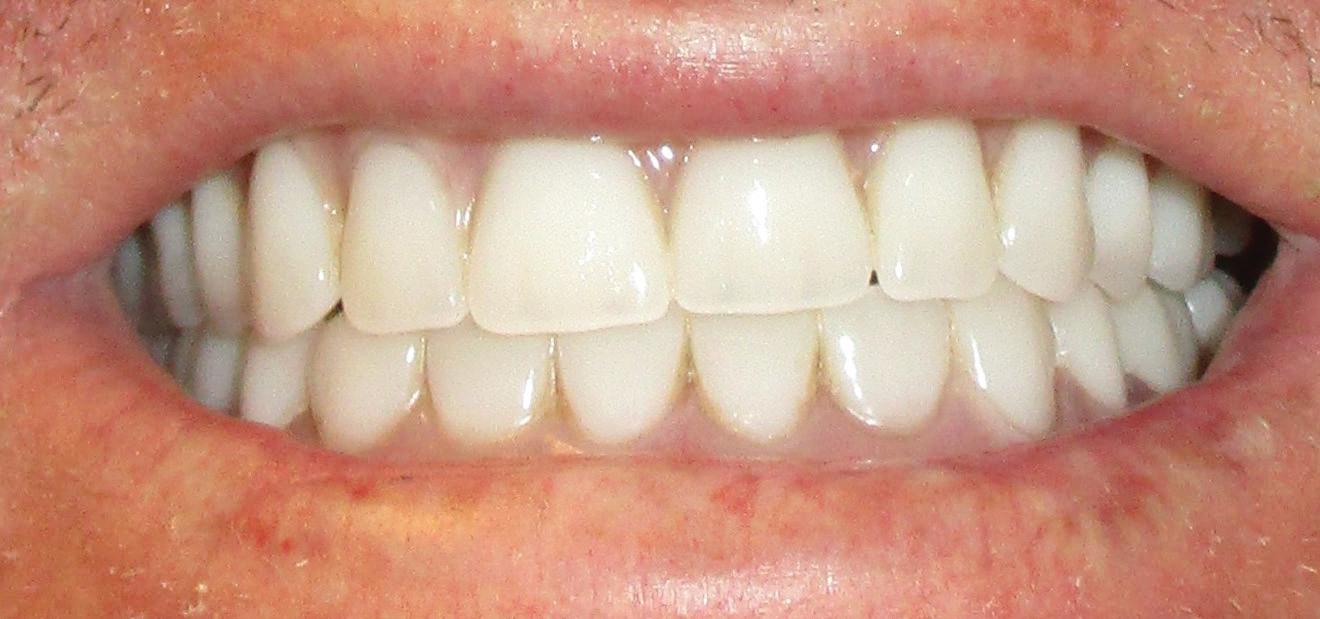

This patient is a 34-year-old male. He works as a dental assistant. His chief concern was, “I have temporary dentures that are six years old. They are discolored and do not fit well. I cannot eat with them.”

Implants were placed in areas of nos. 22 and 27. Implant no. 22 was Nobel Replace RP 4.3x11.5 torqued to 42.1 N/cm; implant no. 27 was Nobel Replace RP 4.3x11.5 torqued to 45.0 N/cm. Due to the patient wearing dentures, cover screws were placed and horizontal mattress sutures were placed. (The ends were clipped after the photos.) The patient was seen two days after and was healing well He was very happy with his treatment.